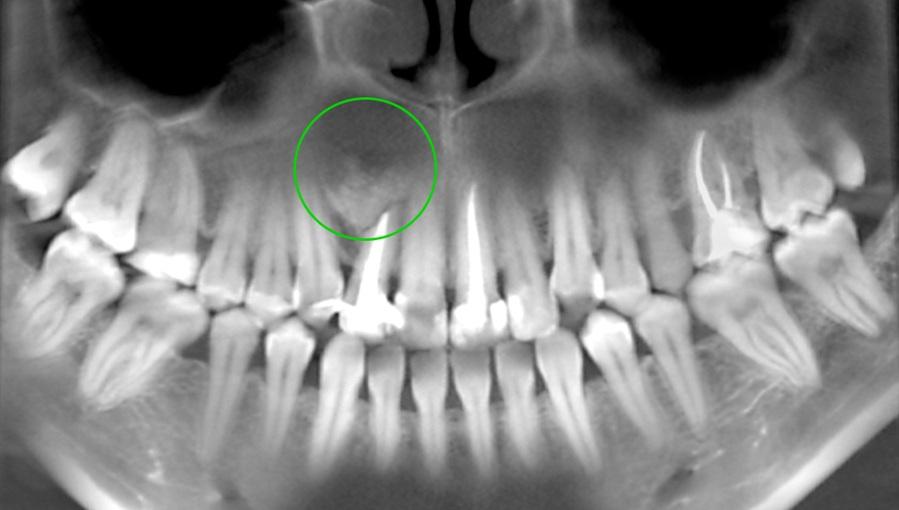

- Рентгенография – панорамный снимок (ОПТГ) или прицельный рентген. Обнаруживают очаг воспаления, разрушение костной ткани, распространение патологии.

- КТ (компьютерная томография). Ее назначают при сложных, глубоких нарушениях, чтобы получить детальное изображение пораженной области, окружающих структур.